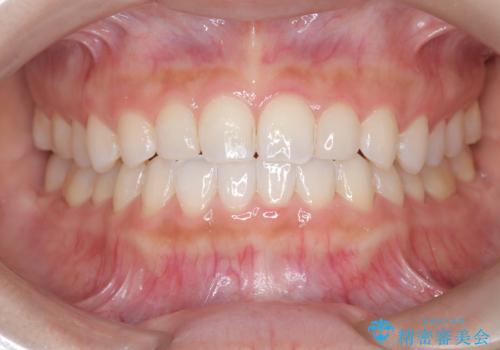

インビザラインを用い、計画通りに歯並びを改善することができました。

矮小歯の幅径を大きくすることで、より理想的な噛み合わせを作ることができます。